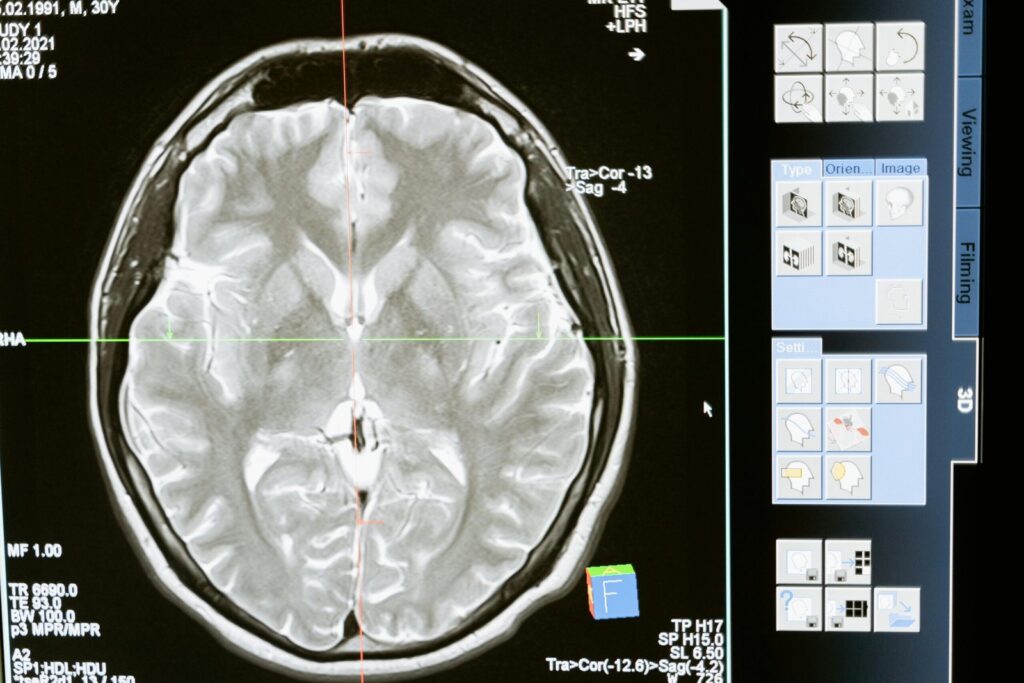

A traumatic brain injury is defined by the Brain Injury Association of America as an alteration in brain function caused by an external force. A non-traumatic brain injury is caused by internal factors, such as stroke or lack of oxygen due to other internal factors such as a hemorrhage in the brain or a brain […]